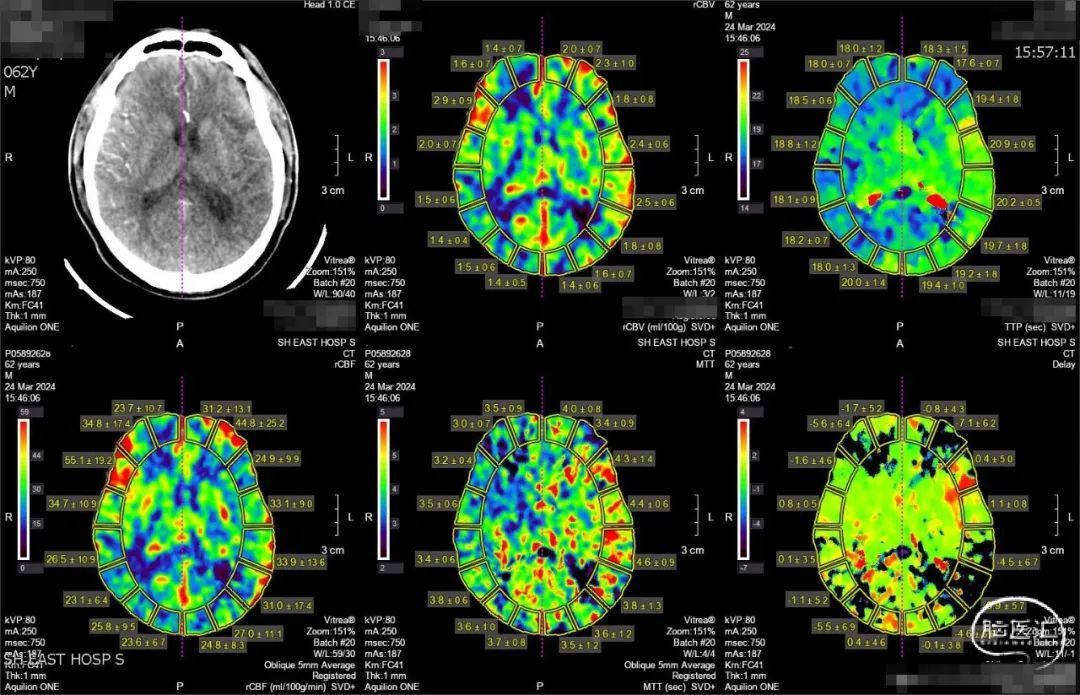

➢ 头颅CT、CTP

左侧大脑中动脉闭塞,左侧大脑中动脉供血区存在低灌注区。

CTP提示左侧大脑中动脉供血区存在大片低灌注区。